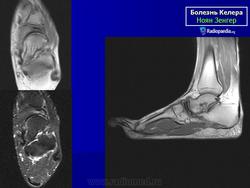

На рентгенограмме в начальной стадии выявляется легкий остеопороз, затем уплотнение костной структуры ядра окостенения ладьевидной кости (ядер окостенения может быть несколько). Появляется сплющивание и фрагментация ладьевидной кости, ее деформация в виде чечевицы или полумесяца. Прилежащие суставные щели расширяются.

Остеохондропатия ладьевидной кости стопы